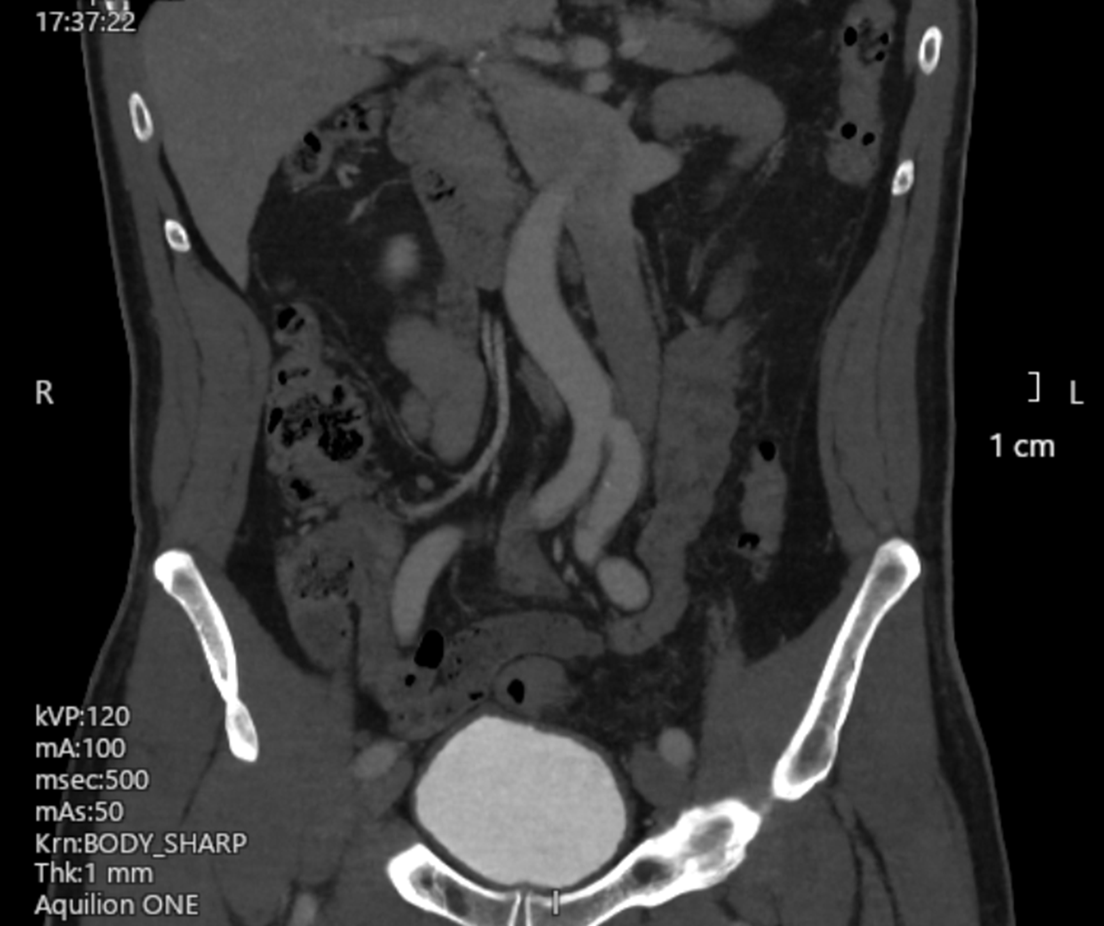

A computed tomography (CT) venogram of the inferior vena cava (IVC) and iliac and femoral veins was arranged. The scan showed a left-sided IVC, which “crossed over” to the right side at the renal vein level (Figure 2). The apparent filling defect was attributable to external compression of the right common iliac vein by the left iliac artery as it crossed to the left side (Figure 3).

Figure 2. (A-C) Three consecutive cuts of coronal plane images (anterior to posterior) from the patient’s computed tomography venogram. The left-sided inferior vena cava is marked with an asterisk. (B) The right iliac vein appeared to be compressed by the left iliac artery (arrow), which may explain the intraprocedural finding.